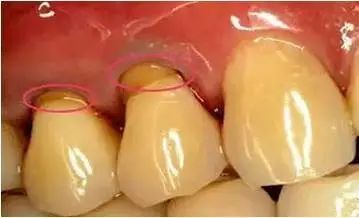

一些看似不经意的举动或者习惯正在毁掉您的牙齿。刷牙是日常最基本的牙齿护理方式,但也许多人因为不当的刷牙方法造成了牙齿的损伤。楔状缺损是口腔科一种常见病。它是在牙齿的颈部靠近牙龈的位置,形成一个呈楔形的形状,因此称为“楔状缺损”。其发展缓慢常被人忽视, 它是在不知不觉中发生的。最常见的病因就是我们在生活中天天的大力横向刷牙 ,长期就会在牙颈部靠近牙龈的位置出现一个横沟,那么身体上最坚硬物质的是什么?没错,就是牙齿。那为什么这么坚硬的牙齿还会出现楔状缺损呢?因为再坚硬的组织,也经不住长年累月、水滴石穿的破坏啊;也因为牙齿的颈部是釉牙骨质界的位置,这个地方的牙釉质覆盖最少,因此牙龈也容易发生炎症或牙龈萎缩导致牙体暴露,所以耐磨能力最薄弱,有利于缺损的发生,这是牙体结构的弊端。